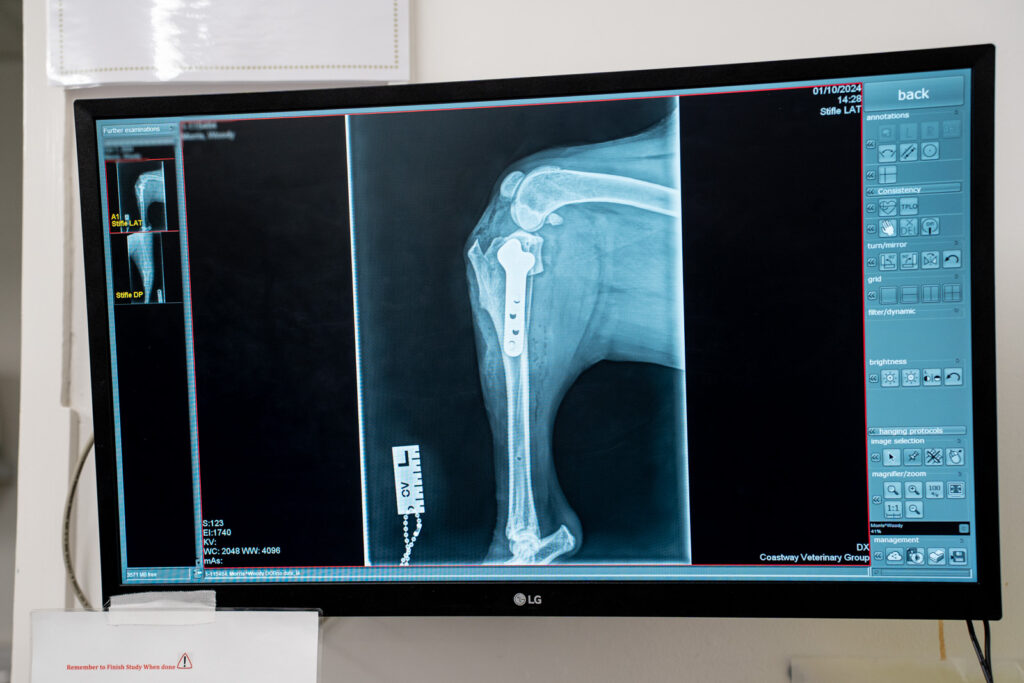

Orthopaedics

- Orthopaedics